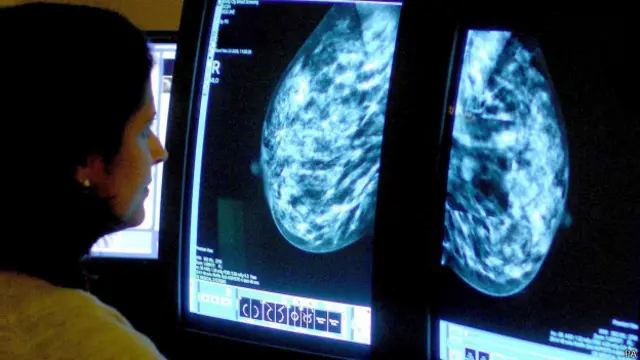

Kadınlarda meme kanseri, erkeklerde ise prostat kanseri en yaygın türler arasında olmaya devam ediyor.